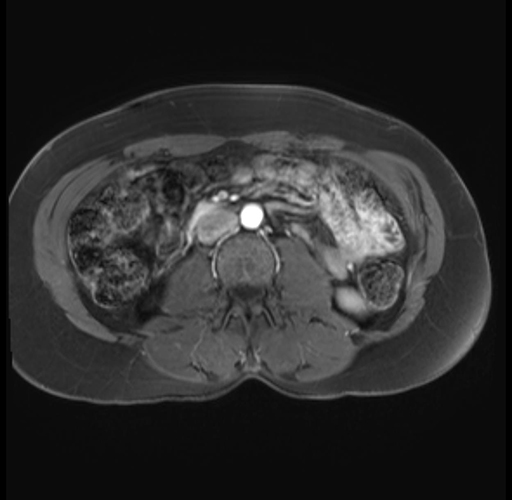

Imaging Analysis

Look through the patient's CT scan to identify any areas of concern for the necessary procedure.

Based on your CT findings, which issue(s) are present and would give reason for "planned slowing down moment(s)" in this case?

Considering a standard distal pancreatectomy procedure, what step(s) of the operation would you do differently in this case?